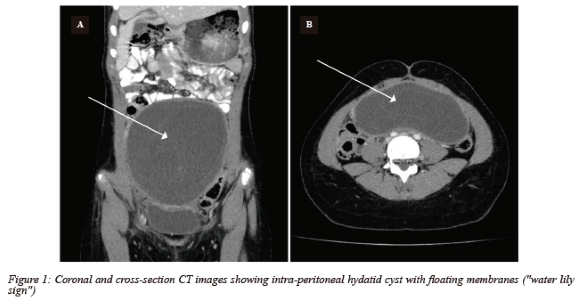

The patient was admitted with a presumed diagnosis of an ovarian cyst. Diagnostic laparoscopy revealed a complex cystic mass, densely adhered to both the bowel and omentum and it was noted that the cyst originated from the peritoneum and not the ovary. Several peritoneal deposits were observed and biopsied and the procedure was terminated to allow for further investigation. Histology results were in keeping with hydatid cyst and subsequent serology revealed a positive Echinococcus ELISA and an IgG value of 28.45 U/ml. The chest X-ray and abdominal ultrasound revealed no extra-peritoneal involvement. Contrast-enhanced computed tomography (CT) scan of the abdomen demonstrated an intra-peritoneal hydatid cyst measuring 147 x 143 x 60 mm extending from the pelvis into the mid-abdomen. There was no free fluid in the abdomen, and all the other abdominal organs appeared normal.

Imaging plays a critical role in the diagnosis of hydatid cysts. Ultrasonography is the most commonly used initial radiological tool for identifying the source organ and characterising hydatid cysts, with a sensitivity of approximately 90-95%.4 Typically, a single unilocular lesion or multiple well-defined anechoic cystic lesions, either with or without daughter cysts, are observed.4 Daughter cysts can be identified by their characteristic internal septations. Hydatid sand, primarily composed of hooklets and scolices, may become visible when the patient changes position during imaging. 4

CT scans exhibit a high sensitivity of around 95-100% for detecting hydatid cysts.4 Contrast-enhanced CT scans reveal well-defined, round lesions with low attenuation and no contrast enhancement.4 Serological testing, particularly Echinococcus ELISA and IgG assays, can be used to assist in diagnosis and should form part of the work-up of all cystic abdominal lesions in endemic areas.4